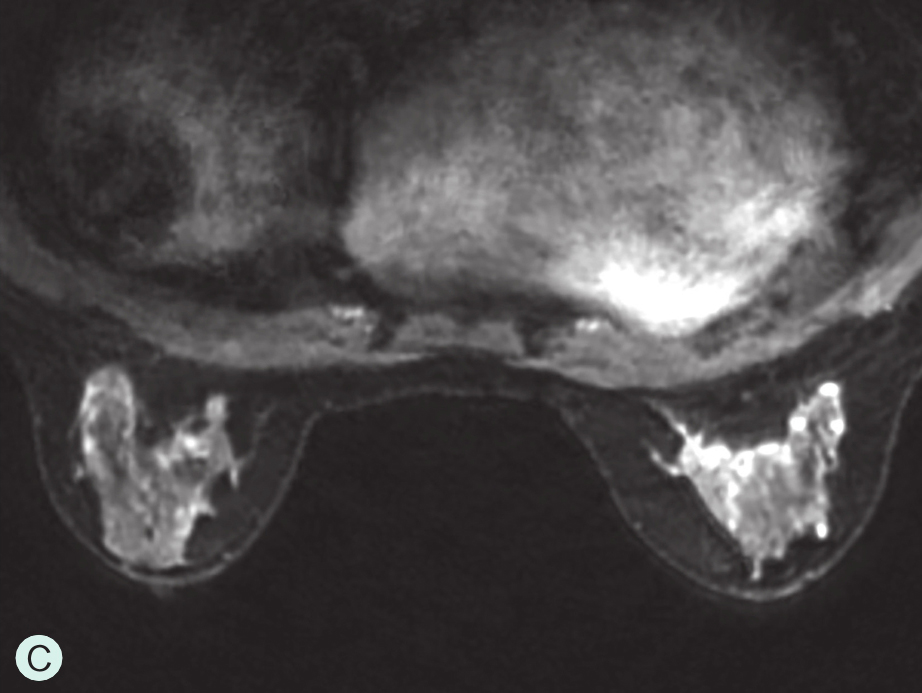

图1-4-3 CEUS时不同乳腺腺体增强强度

A.CEUS背景极少强化;B.CEUS背景轻度强化;C.CEUS背景中度强化;D.CEUS背景重度强化